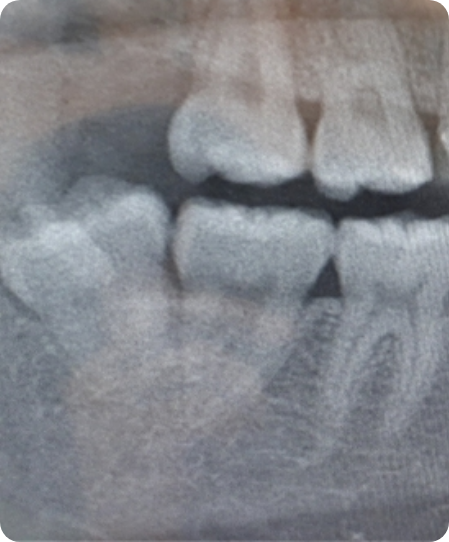

複雑な生え方をしている親知らずは口腔外科で

親知らずは一番奥の歯(前歯から数えて8番目の歯【智歯(ちし)】とも呼ばれる歯)で お手入れが難しく、虫歯になりやすい歯です。また歯並びによっては横や斜めに生えてきたり、 骨の中に埋まったまま生えてこない場合もあり、将来的に炎症、痛みが発生することもあります。 そのため、親知らずの抜歯はとても大切な治療と言えます。親知らずの抜歯は一般歯科で対応が難しい場合、 総合病院などの大きな病院の口腔外科専門医が治療にあたります。 当院では一般歯科で対応が難しい場合でも、口腔外科専門の歯科医師が所属していることから連携がとりやすく、 他の医院に比べ、親身な対応が可能です。お困りの方は是非一度ご相談ください。